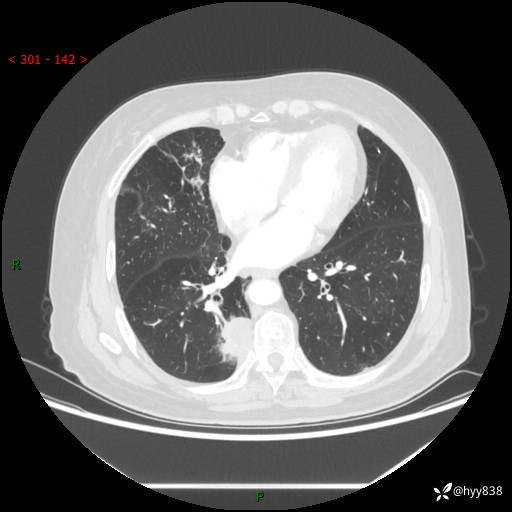

胸部CT肺窗(平扫外院)

辅助检查:CT

临床诊断:肺肿物